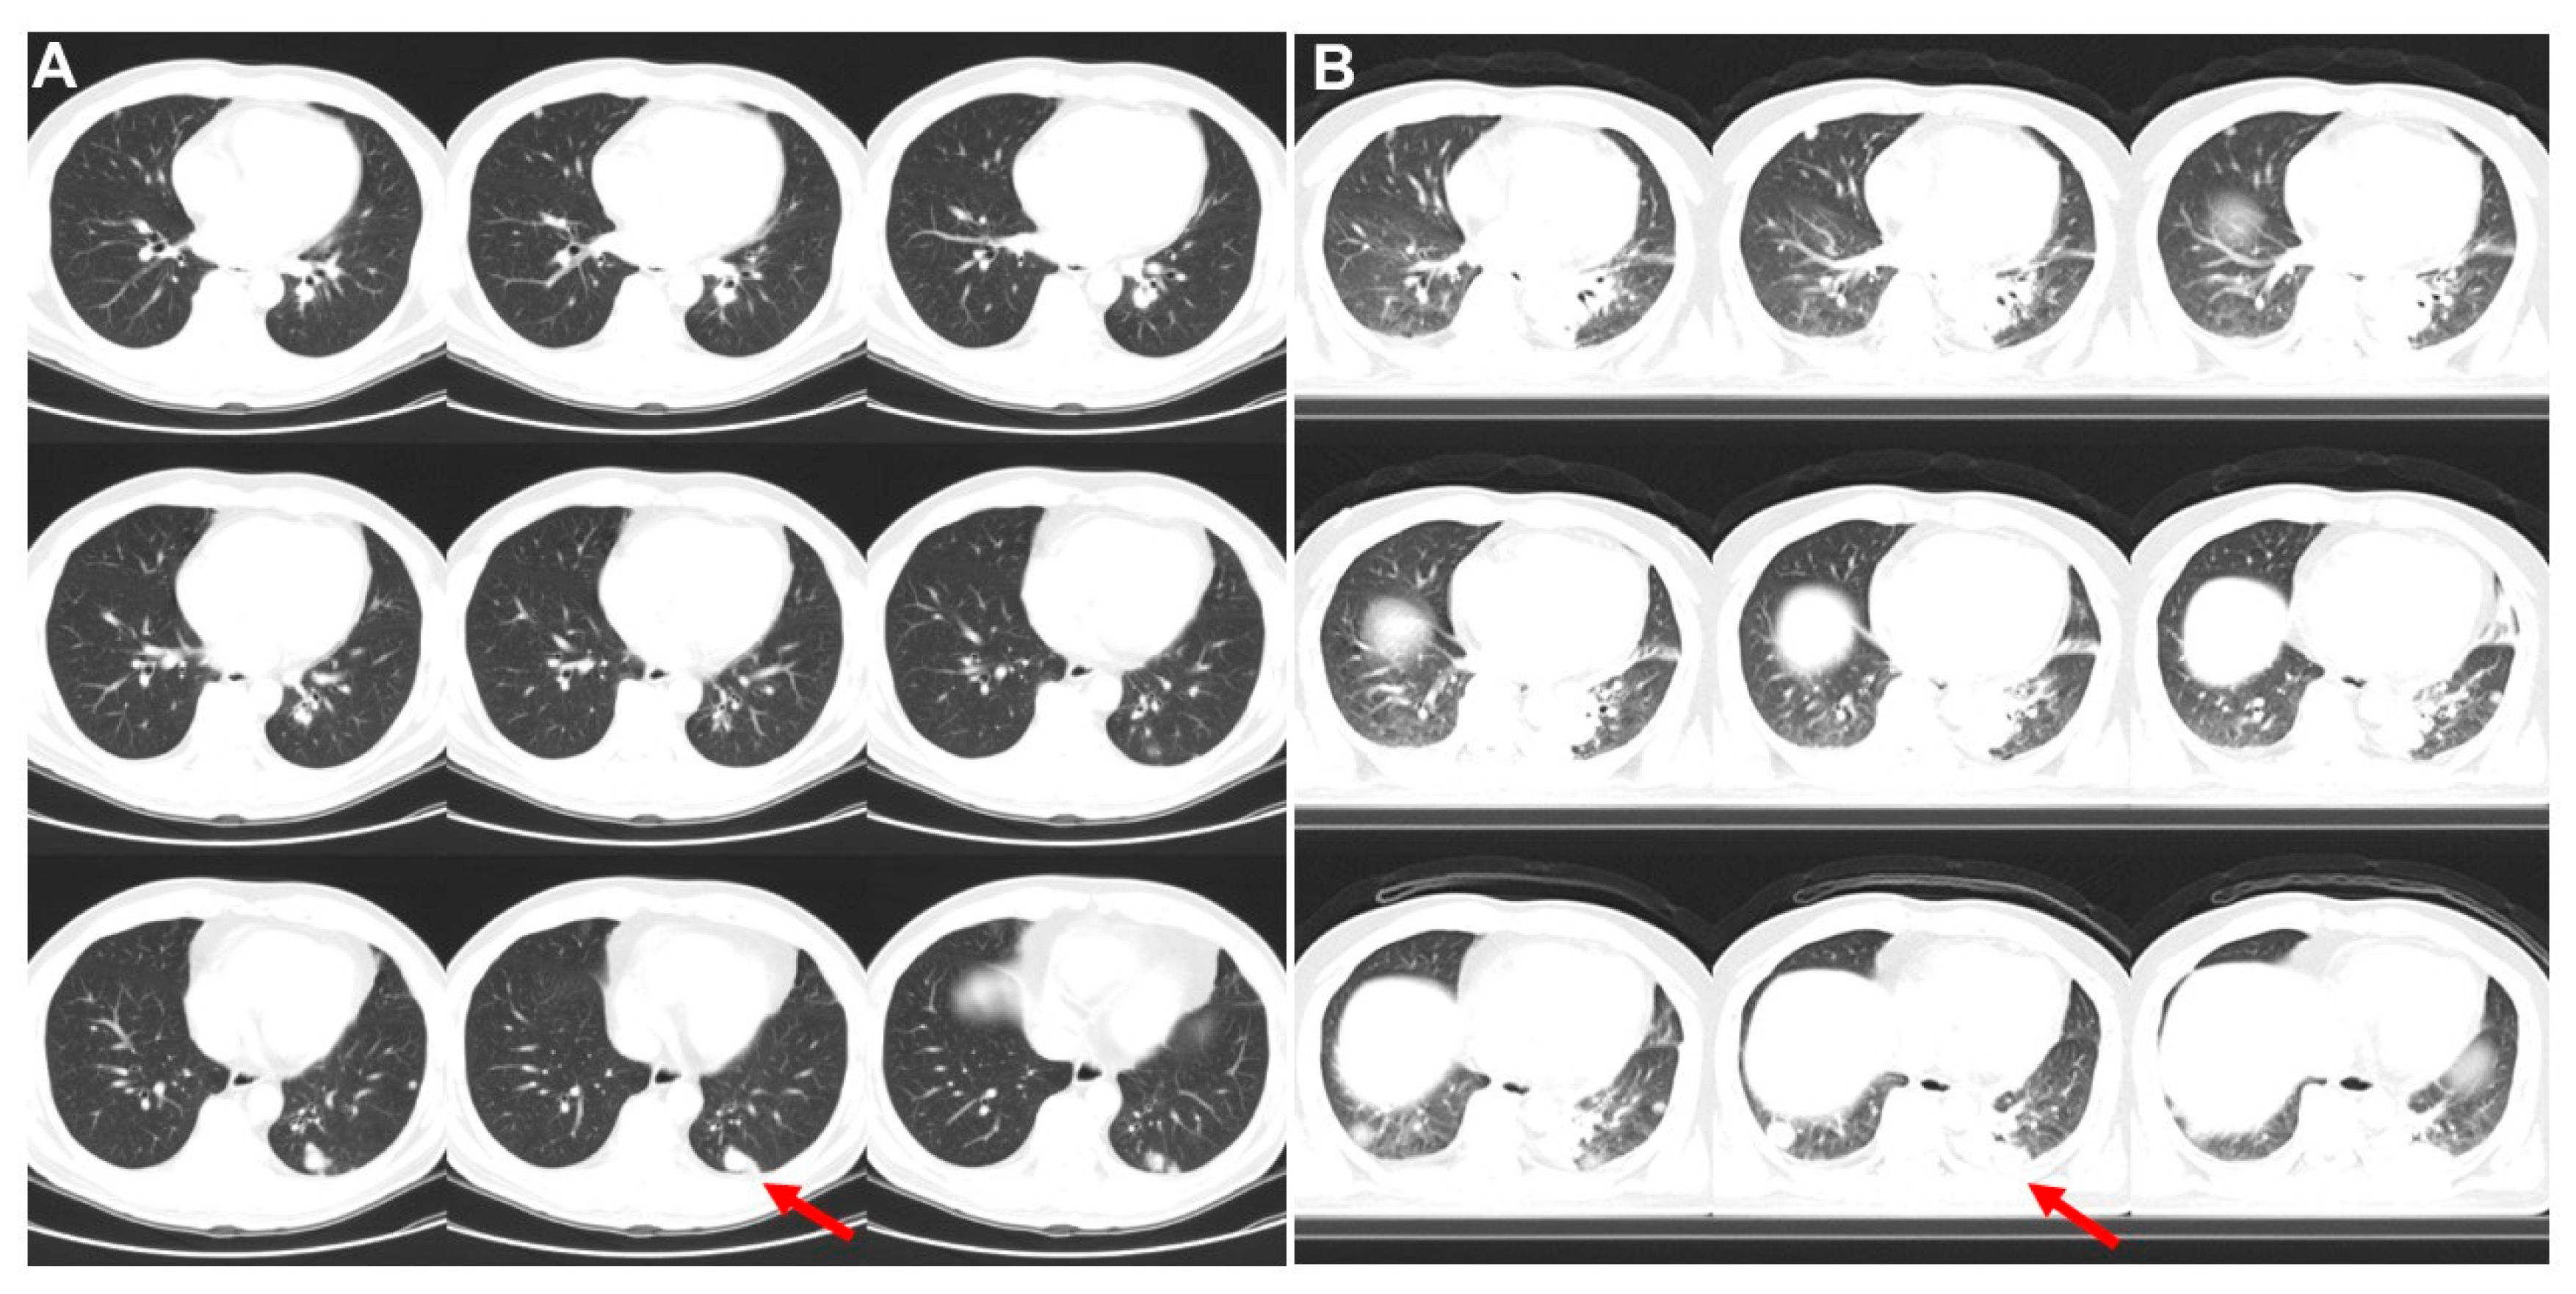

Figure 2. Three months and 21 days later, a series of transverse CT images (A) from left to right and up to down revealed the left lower lung lesion (1.1 cm; arrow) and contact to pleura on lung window. A small node close to aorta was also noted. Besides, small nodular lesions involving the mediastinal, lung and liver were detected. He received biopsy and histopathological study showed left lower lung adenocarcinoma. A further 11 days later, 2nd FDG PET/CT was performed. CT images (B) revealed the left lower lung lesion was enlarged (3.1 cm; arrow) and spread to aorta margin and pleura. Bilateral lung nodules also became enlarged. To get an idea about how fast lung cancer grows, it’s helpful to look at doubling time [2,3]. Since the left low lung lesion grew from 1.1 × 1.1 × 0.7 cm by CT scan to 3.1 × 1.9 × 1.5 cm by 2nd PET/CT scan, its doubling time was 4 days.

Diagnostics 13 02706 g002